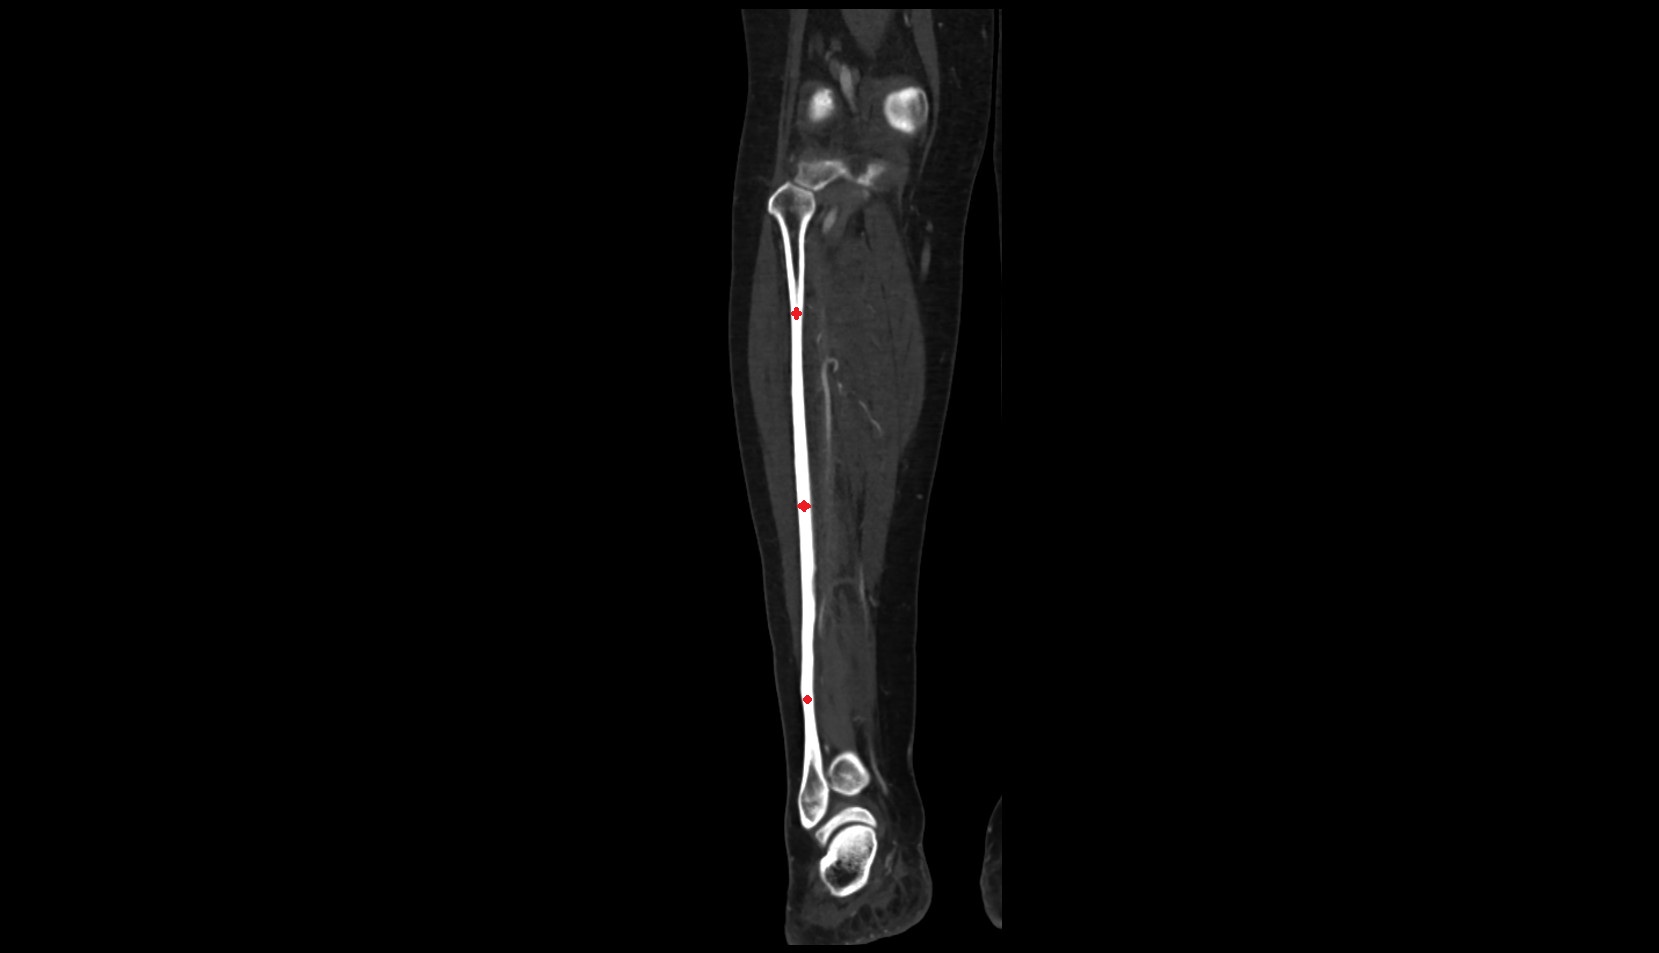

- Body of tibia

- Tibia

- Fibula